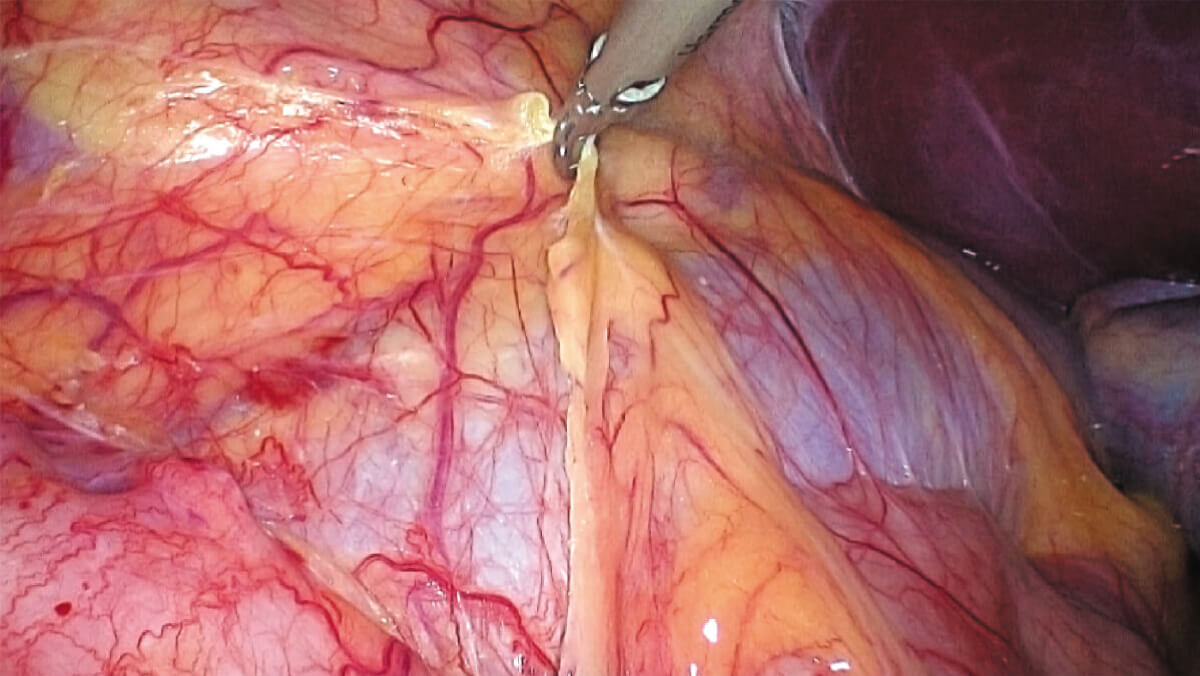

白光与荧光像素级匹配

结合自研镜体齐焦技术

多种成像模式随意切换不移焦

表面细节不遮盖

边界清晰,利于切缘评估

细微结构无伪影

避免术中误伤

荧光信号强弱分明

精准辅助临床决策

术中实时多维导航,领航诊疗一体新标准